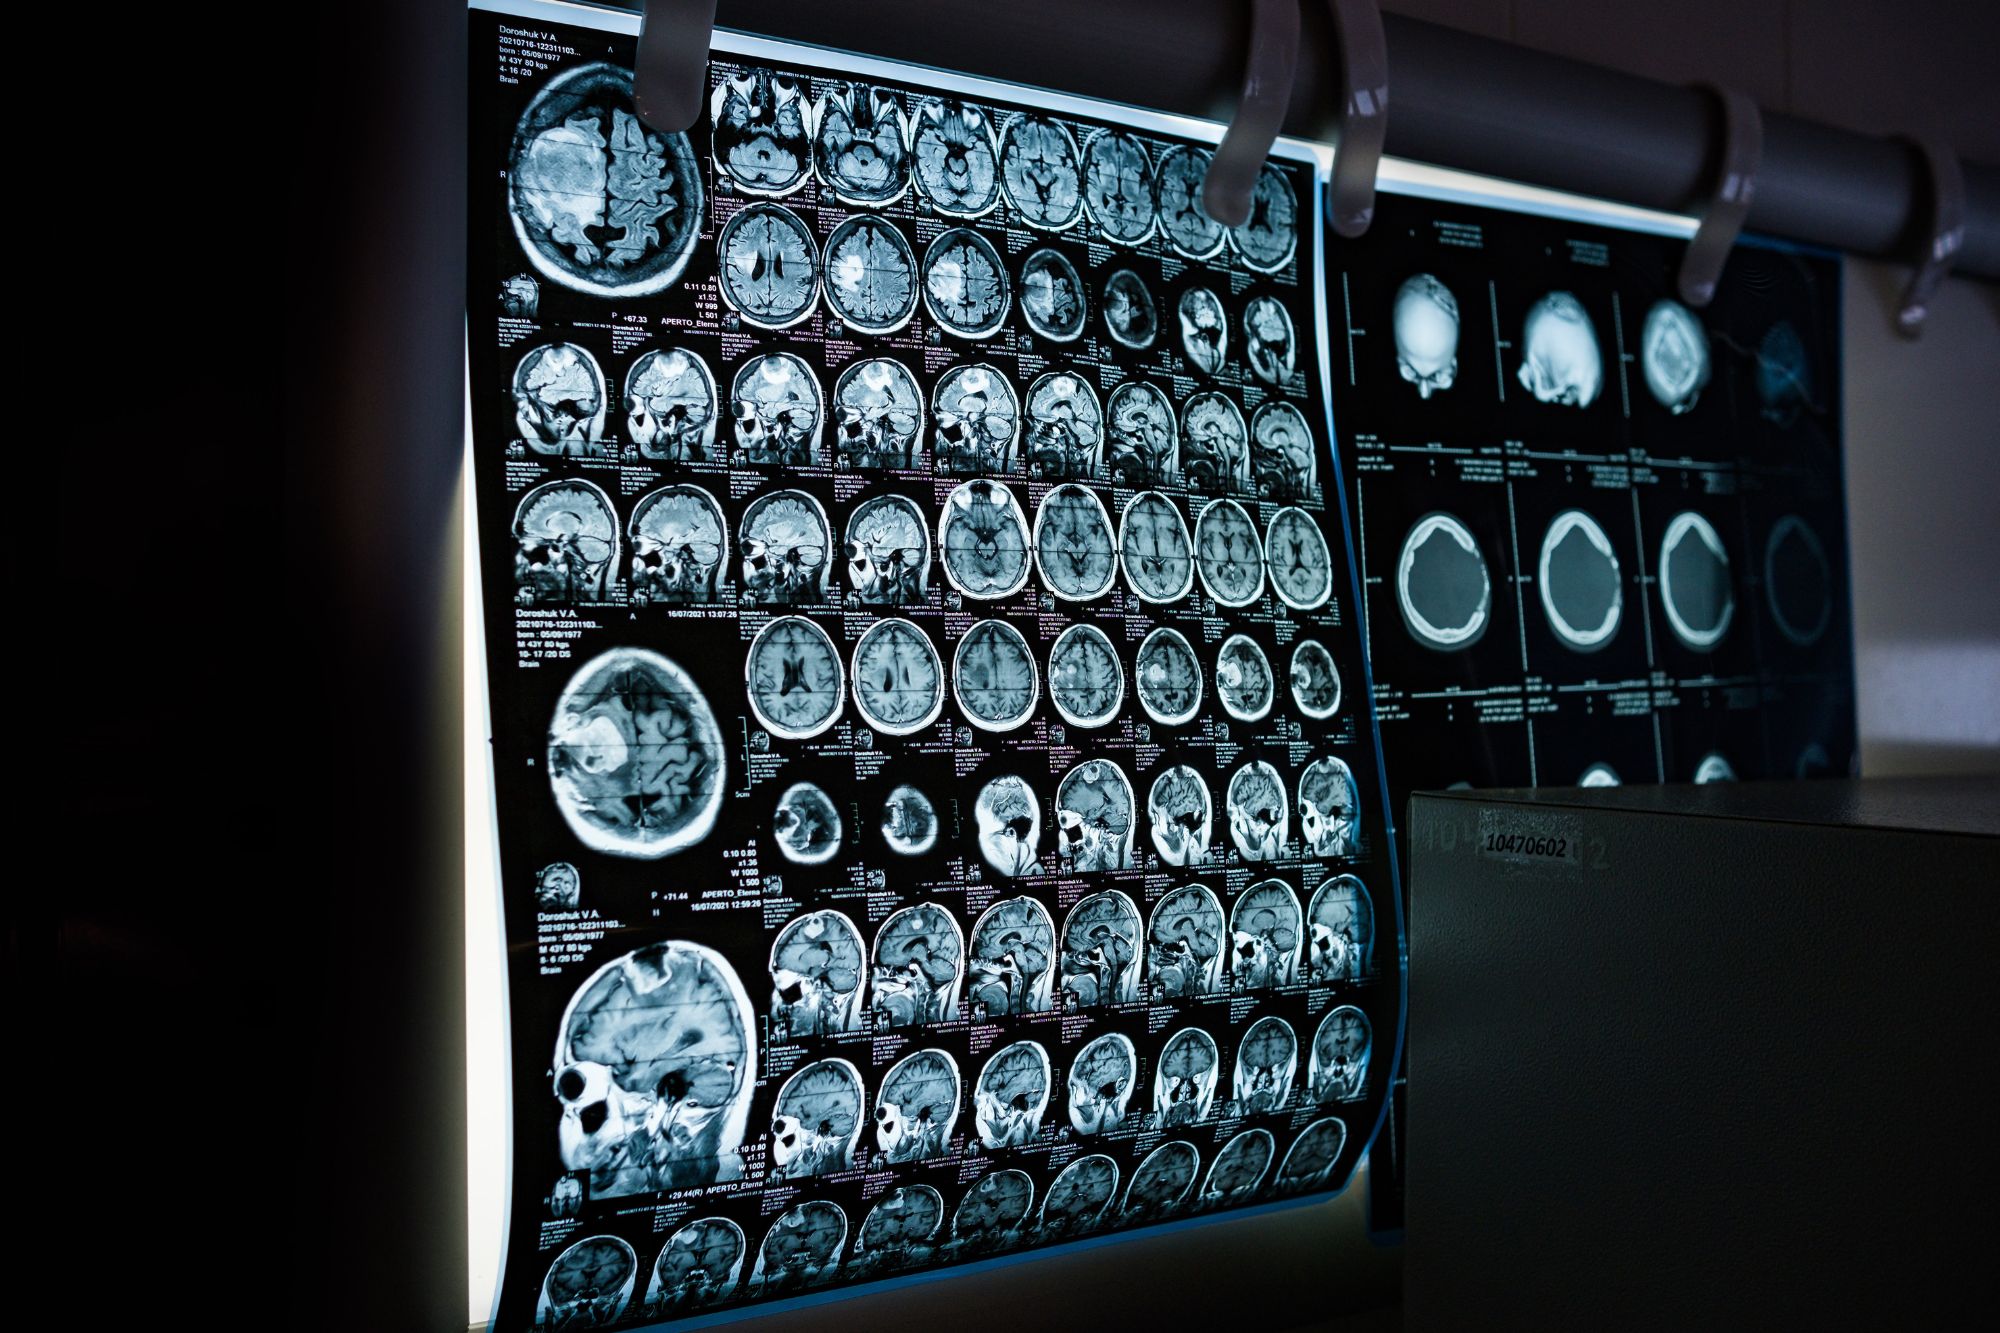

Donne e uomini sono davvero così diversi come siamo abituati a pensare? E bene, per secoli abbiamo alimentato il mito che i cervelli maschili e femminili fossero mondi alieni e incompatibili. Oggi, una ricerca pubblicata sulla rivista Science demolisce i cliché e ci consegna una realtà molto più sfumata e affascinante: non siamo pianeti diversi, ma lo spartito genetico dei nostri neuroni viene “suonato” con un volume leggermente differente a seconda del sesso biologico.

L’atlante da un milione di cellule

Lo studio, guidato da Alex R. DeCasien del National Institute of Mental Health, rappresenta una novità per le neuroscienze. I ricercatori hanno analizzato circa 1,2 milioni di cellule provenienti da sei diverse regioni della corteccia cerebrale di 30 donatori. Grazie a tecnologie di trascrittomica, la disciplina biologica che studia l’insieme completo degli Rna messaggeri presenti in una cellula, tessuto o organismo a singola cellula, il team ha potuto osservare l’attività di 680.000 neuroni eccitatori, 290.000 neuroni inibitori e centinaia di migliaia di cellule gliali, le instancabili “assistenti” del cervello.

Il risultato è una mappa ad altissima risoluzione che identifica dove e come i cromosomi sessuali e gli ormoni lasciano la loro impronta molecolare.